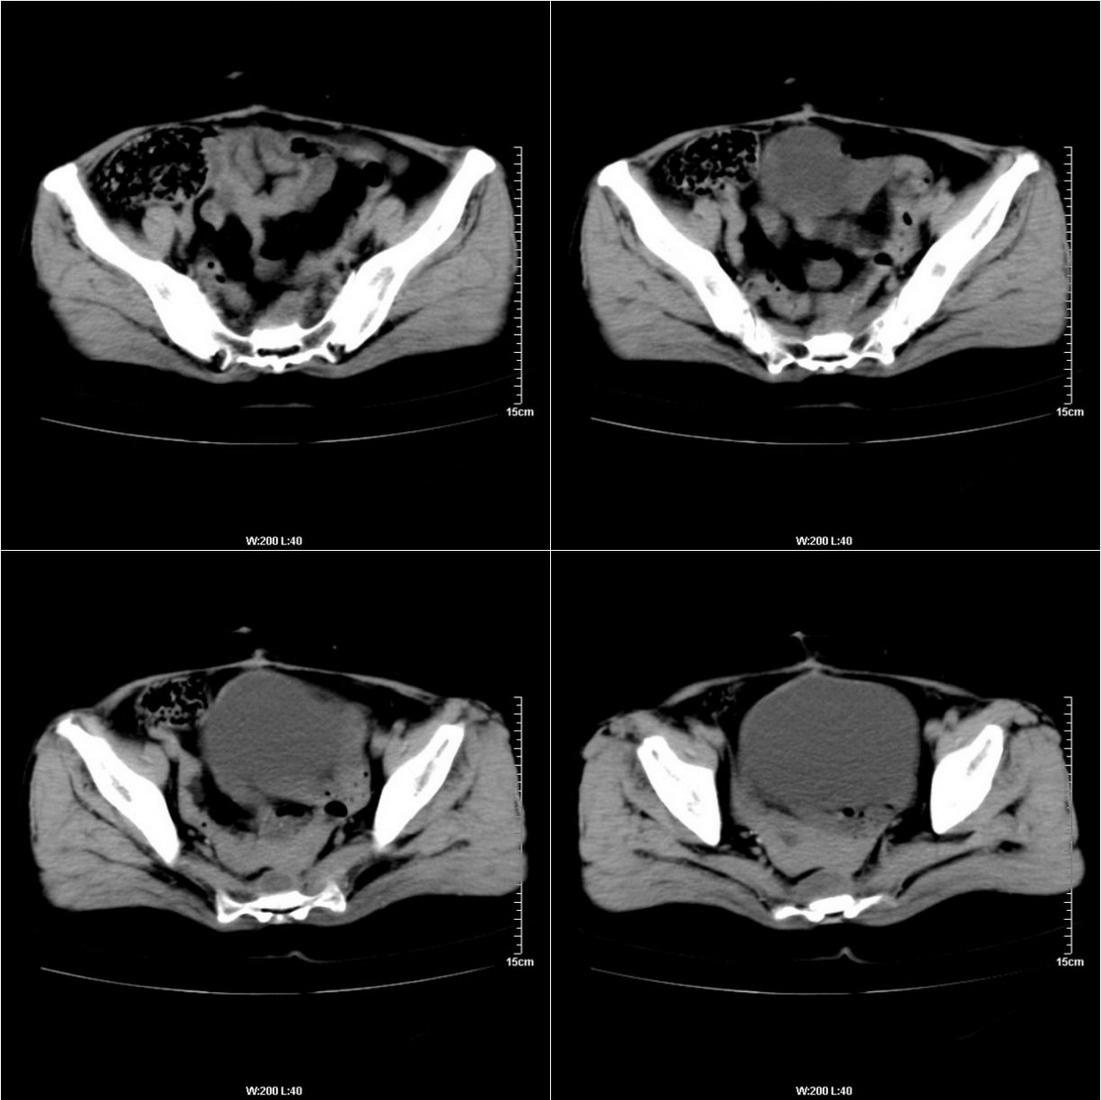

不知道病人的直肠癌手术方式如何,直肠已经全部切除,乙状结肠造瘘于左下腹,肛门应该也没有保留吧?如此,应该是复发了:

病变于肛尾韧带、右侧坐骨肛门窝内并顺右侧肛提肌向右侧闭孔内肌蔓延,骶前软组织内也形成了肿块,麻烦啊!

典型直肠癌术后骶骨前转移复发.

膀胱壁见索条状软组织密度影伴强化,可考虑炎性肉芽肿样增生改变,常见于放疗后或慢性感染;直肠及周围软组织见肿块,轻度强化,考虑直肠癌术后复发,并侵犯周围组织

考虑直肠癌术后复发并侵犯周围组织。